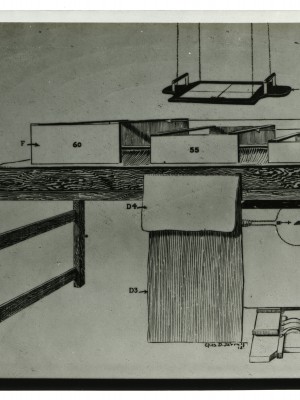

Dr. Edwin Ernst, an only child born to St. Louis residents Charles and Catherine Ernst, was a notable Roentgenologist, a physician who specializes in radiological work. Dr. Ernst studied at Washington University in St. Louis and later at Moravian College in Bethlehem, Pennsylvania earning his advanced degrees. For two years he served as a resident physician at the St. Louis Mullanphy Hospital before leaving to pursue a private practice. When the United States formally entered the war in 1917, Ernst left St. Louis to become chief radiologist at Base Hospital 21. He was discharged honorably in 1919 with the citation of Major. His collection consist of x-ray images taken at Base Hospital 21 as well as drawings of radiological equipment and photographs.